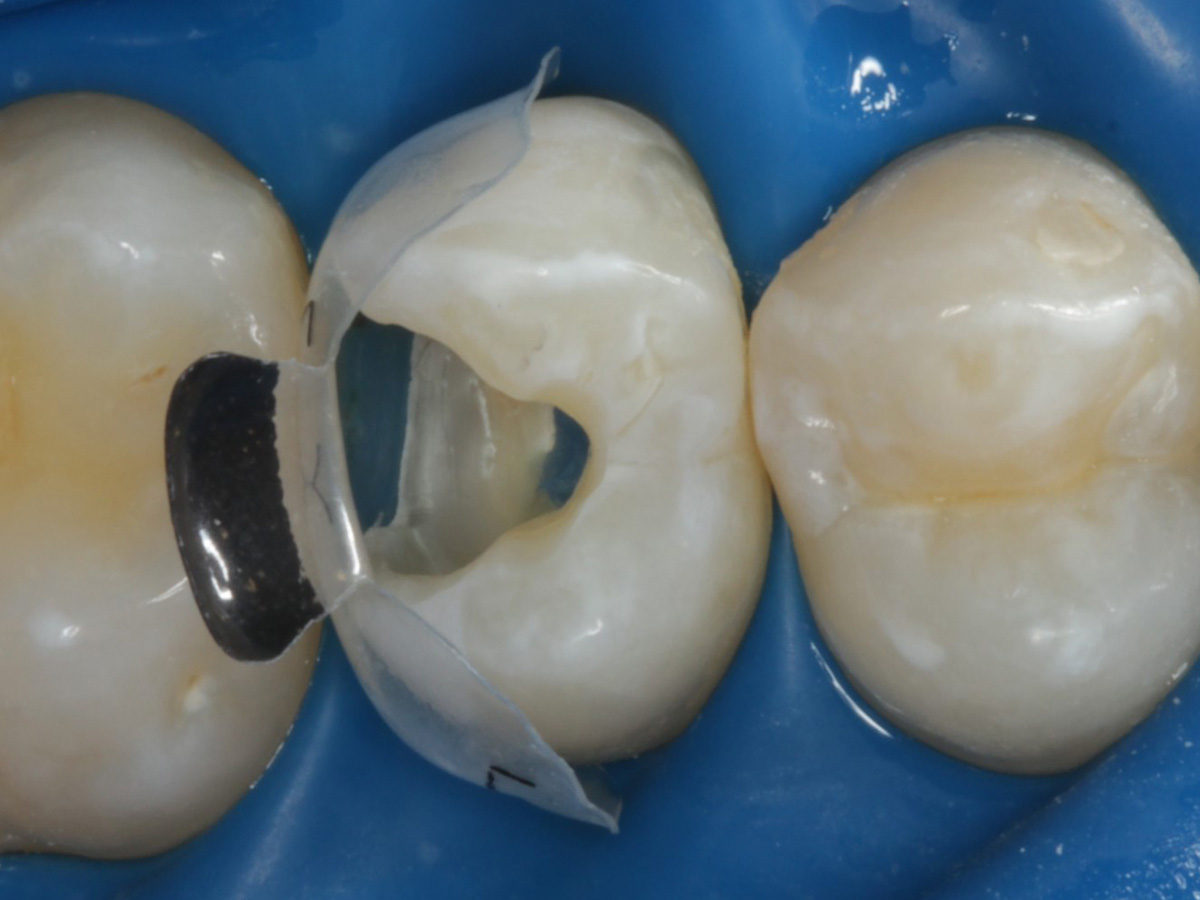

Abbildung 6

Pulpenkavum mit Watte und farbigem Komposit abgedeckt; zuvor Spülung der Wurzelkanäle nur mit NaCl zwecks Nichtgefährdung der Kompositadhäsion